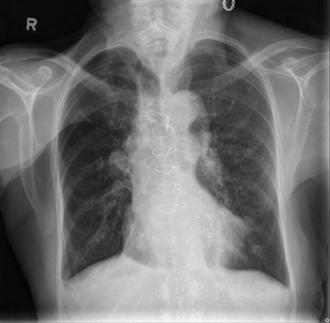

A 78-year-old male presents to the emergency department with an unstable bradycardia. The patient deteriorates from a second degree, Mobitz Type II-AV block into a third degree AV block requiring ACLS protocol medications, transcutaneous pacing, and ultimately transvenous pacing until definitive management with a permanent pacemaker can be arranged.

First EKG for the case: